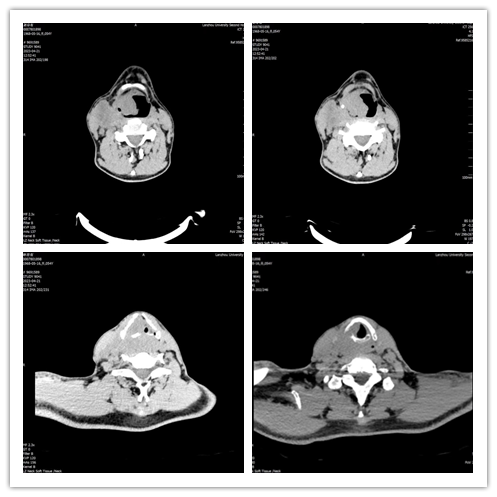

术前颈部CT

患者54岁,男性,因声音嘶哑、气短2月、呼吸困难2天就诊,以“喉肿物、呼吸困难”急诊入院。入院后,段世宏主任团队结合患者病史及临床表现,完善相关检查后确诊为下咽癌侵犯喉和右侧甲状腺及颈内静脉,伴右颈部淋巴结转移。经过充分讨论及精心准备,5月7日,联合口腔科孙健主任共同为患者实施了全喉及全下咽切除+右侧根治性颈淋巴结清扫+右侧甲状腺叶及峡部切除+胸大肌皮瓣修复手术,手术全程用时12小时,术后患者恢复良好,已康复出院。

该患者由于肿瘤转移,多处侵犯,手术范围广,病损切除面积大,涉及劲内静脉、劲总动脉、甲状腺、甲状旁腺等重要组织、器官,术中创面大,修复困难,易造成大出血、大面积感染及修复皮瓣坏死,甚至休克、死亡风险。